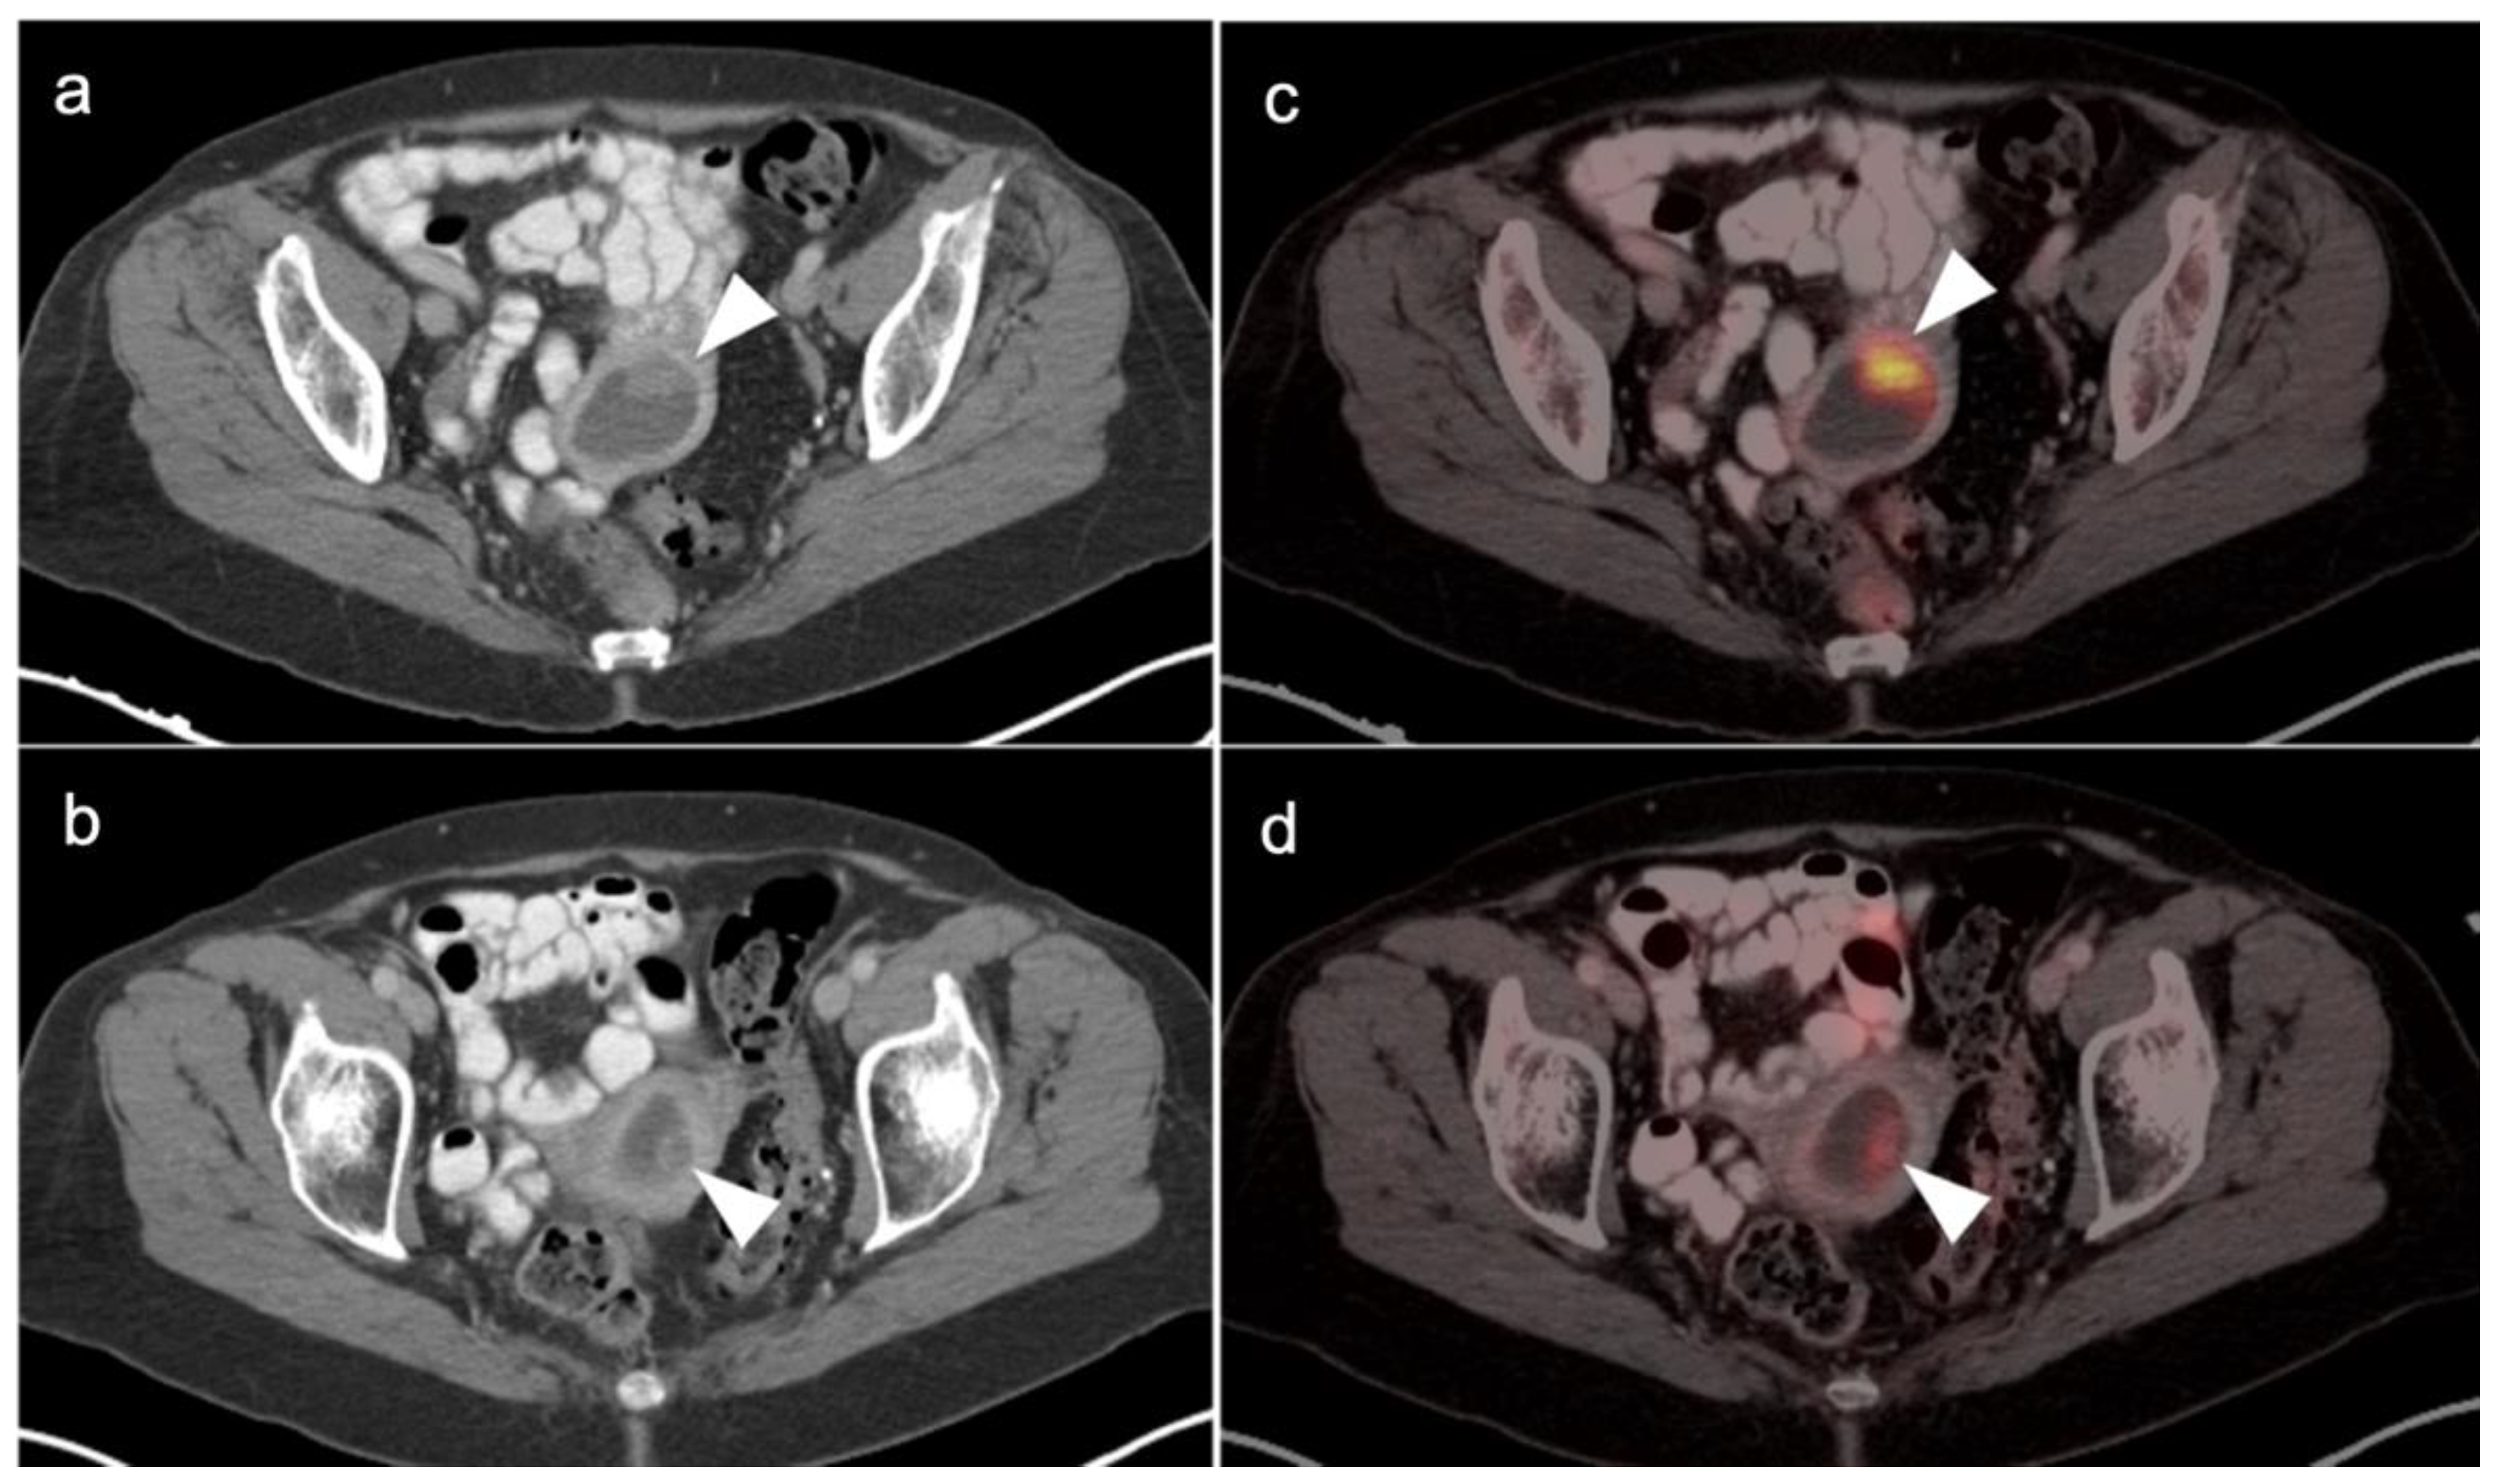

3.2. Urothelial Carcinoma